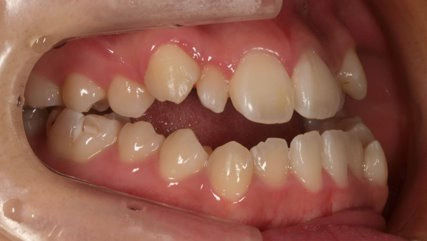

上顎前突といわれ、上顎の前歯が唇側に出ている状態を言います。

前歯が出ることで見た目の問題もありますが、口を閉じることができない、口呼吸をしてしまう、外傷などのリスクがあります。

日本人に叢生の次に多い不正咬合と言われており、自然に治ることはありません。また上の前歯が出ている事だけが気になるかもしれませんが、多くの場合、上顎の奥歯の位置に問題があることが多く、部分矯正でなく根本的な治療をした方がいい場合が殆どです。

口を閉じることができないことで、鼻呼吸でなく口呼吸をしてしまい、結果、成長期の場合顎の骨の成長を邪魔してしまうとも言われております。その他、口呼吸はアトピーなどを含むアレルギー症状の悪化、風邪を含むウイルス性の感染症にかかりやすいなどのリスクも増大してしまいます。

歯並びだけでなく全身への影響も多い為、早期の治療をおすすめ致します。